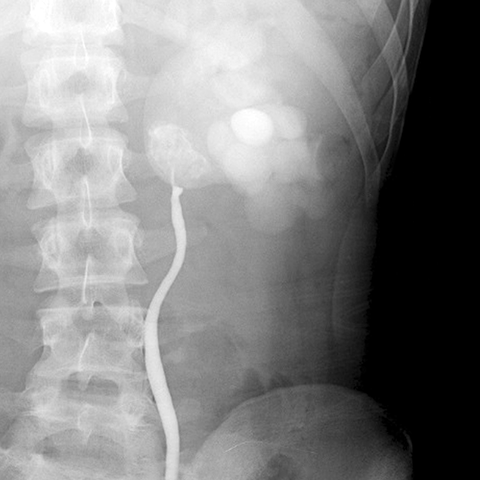

Hydronephrotic kidney [1 of 4]